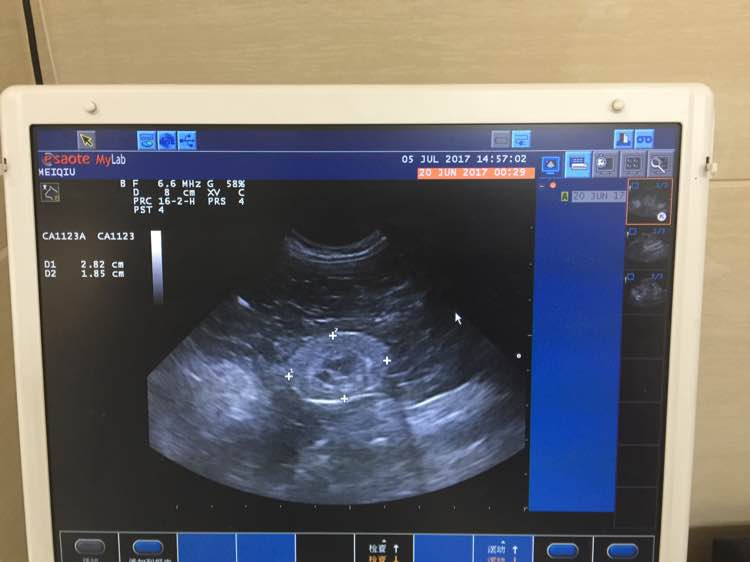

这是最近吃药补液检查结果的对比,分别做了血常规检查,血生化检查,血气检查,血压测量,肾B超,肾及膀胱X光~

7月5日,又带孩子去复查,贫血和脱水都好了,但是肌酐又回到3开头,医生说算是很稳定了,血酸中毒也有好转,测了血压,因为不是动脉测量,所以准确率不高,需要分五次取平均值,血压带包在孩子尾巴上,前三次紧张的血压越来越高,第第四次开始我摸着他告诉他没事,就开始逐渐降下来了,平均值是高于正常值的,但医生也说觉得他并没有高血压症状,暂时高是太过紧张造成的,可以不用吃降压药,我询问了是否可以自己给孩子洗牙,医生说牙结石确实是个严重的问题,如果他要是能配合我就可以自己给他洗。